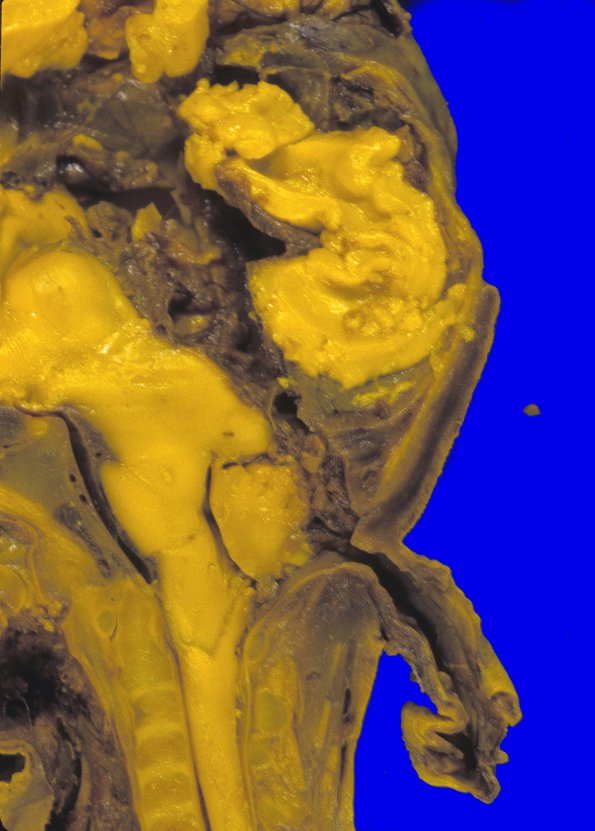

15A2 Encephalocoele (Case 15) 2

Higher magnification of image #15A1.